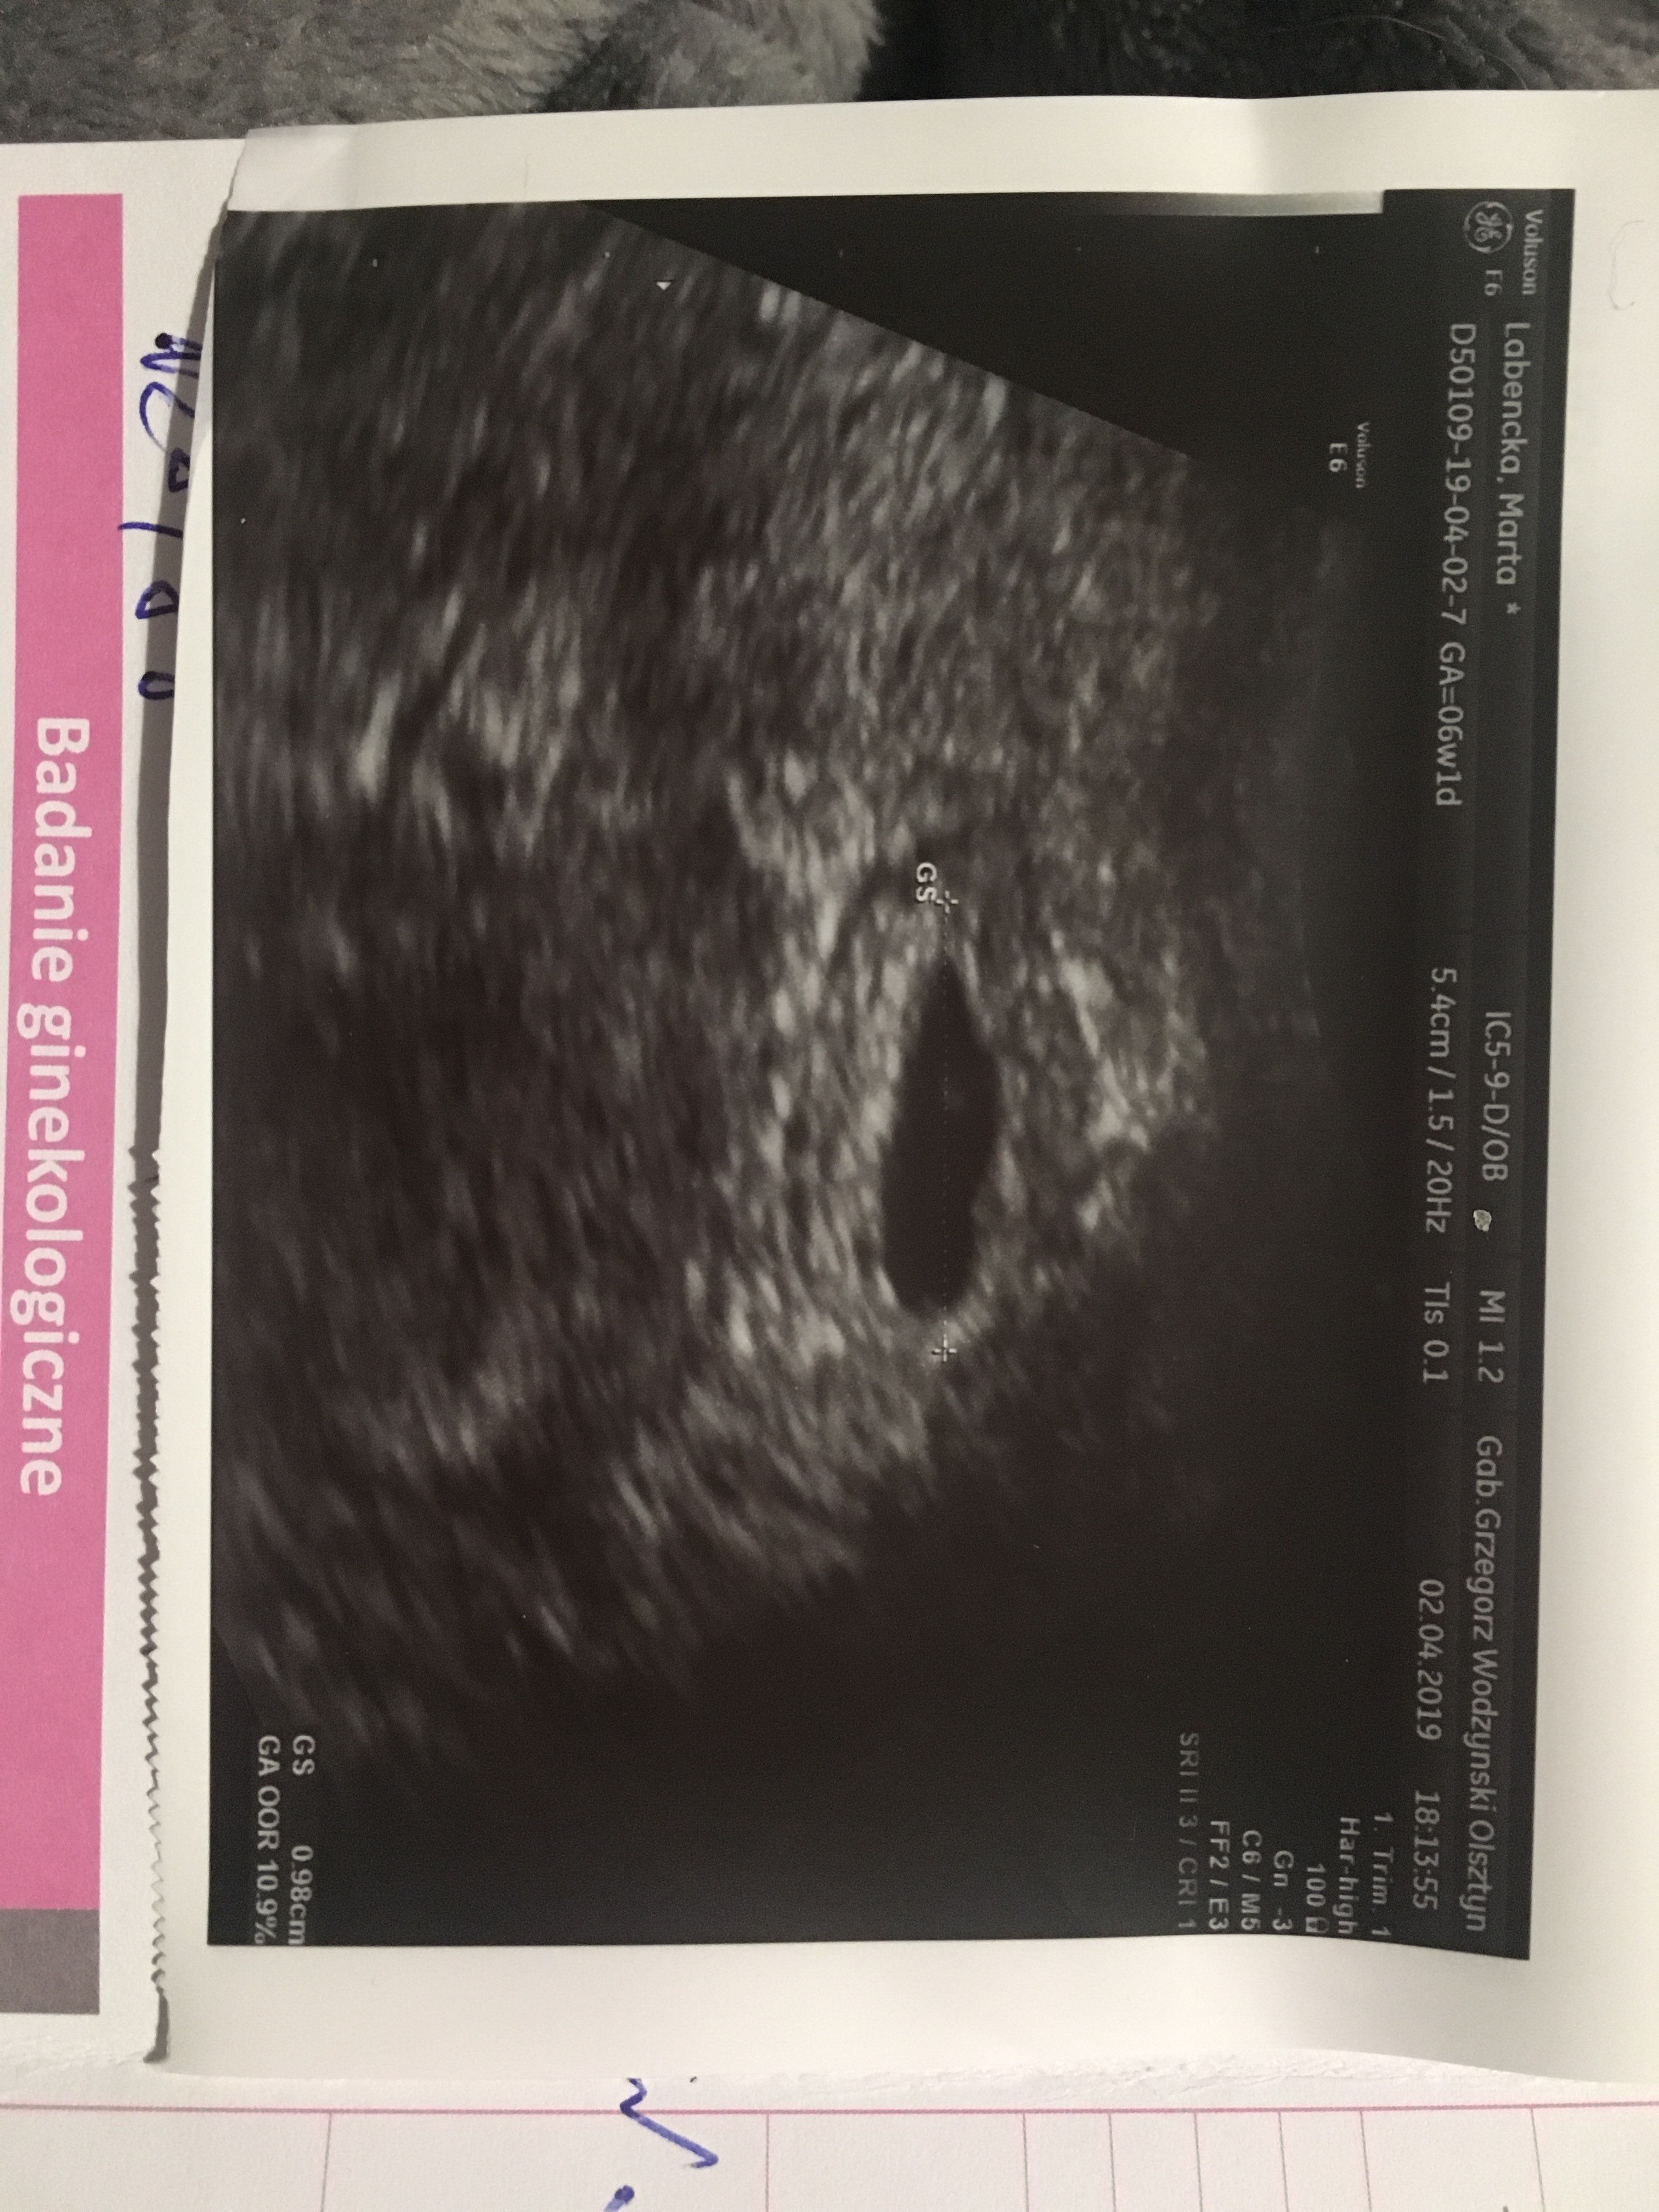

Cześć dziewczyny, wracam z wizyty z wieściami! Jest pęcherzyk, plamienia może od leków przeciwzakrzepowych, może od łyżeczkowań. W pęcherzyku nie ma nic, oprócz jakieś plamki. Czy któraś z was może jest ekspertem od usg? Czy to jest normalne, ze na tym etapie nie ma jeszcze zarodka? Ciąża młodsza na pewno od terminu OM o co najmniej jakiś tydzień. Następna wizyta za tydzień.

Cześć dziewczyny, wracam z wizyty z wieściami! Jest pęcherzyk, plamienia może od leków przeciwzakrzepowych, może od łyżeczkowań. W pęcherzyku nie ma nic, oprócz jakieś plamki. Czy któraś z was może jest ekspertem od usg? Czy to jest normalne, ze na tym etapie nie ma jeszcze zarodka? Ciąża młodsza na pewno od terminu OM o co najmniej jakiś tydzień. Następna wizyta za tydzień. Zobacz załącznik 958371